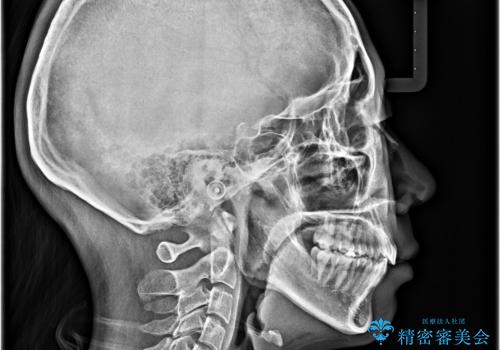

- 口元の閉じにくさを気にして来院された患者様です。

上下ともに歯列が前方に突出していたため、上下左右の第一小臼歯4本を抜去し、ワイヤー装置による矯正治療を行うこととしました。

舌の突出癖による影響もあったため、舌のトレーニングを並行して実施しました。

舌の突出癖がなかなか改善されず、上下前歯の接触がやや甘い状態での仕上がりとなりました。

接触が甘い場合、上顎前歯の叢生が後戻りを起こしやすくなるため、治療終了後の保定期間でも舌のトレーニングを継続するように指示しています。